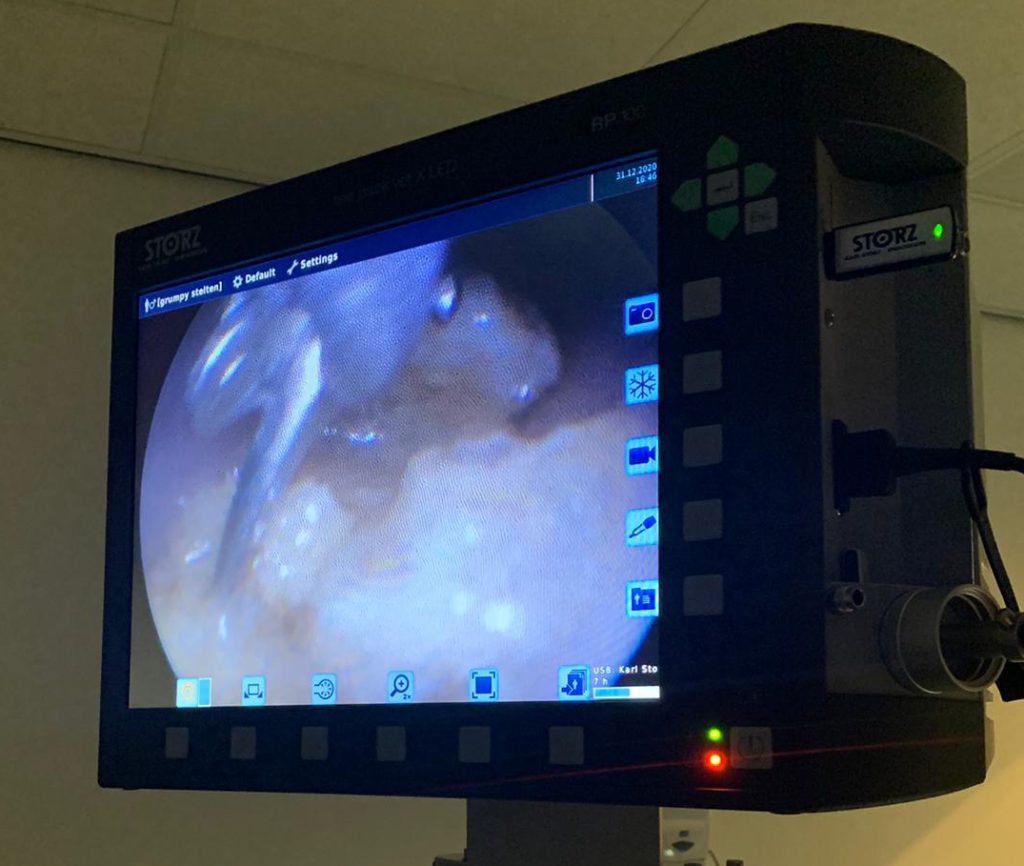

Gelukkig hadden we niet alleen al veel scopen in huis, maar sinds een week ook een compleet nieuwe scoop met nieuwe tangen. Deze heeft op die oudjaarsavond direct zijn dienst bewezen!

Nadat we al 1,5 uur bezig waren en tot de conclusie kwamen dat dit heel lang zou gaan duren, bedachten we ineens dat er nog een andere tang op de praktijk aanwezig was. Deze tang was voor iets compleet anders bedoeld en niet via de scoop te gebruiken, maar het was de moeite waard om te proberen of deze nog kon helpen.

En inderdaad, met behulp van deze tang, die we langs de scoop inbrachten, konden we hierna de stukken in een paar keer verwijderen. De slokdarm was niet beschadigd en zowel de eigenaar als wij konden nog op het nippertje de jaarwisseling vieren.